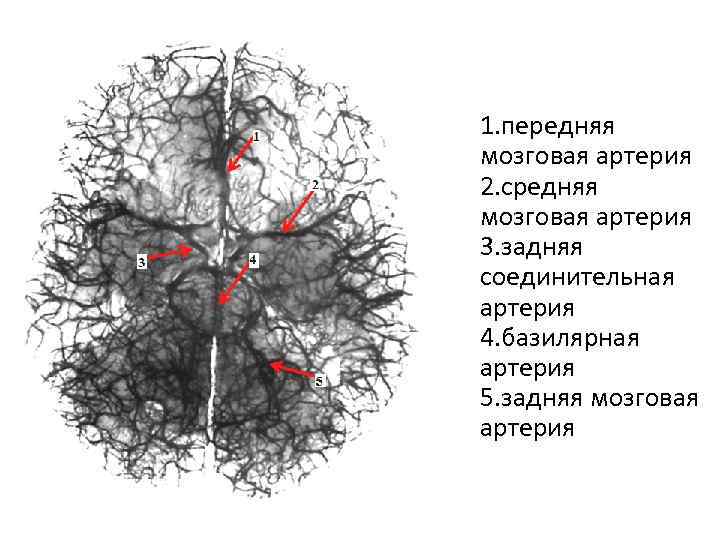

Анатомия: Задняя соединительная артерия мозга